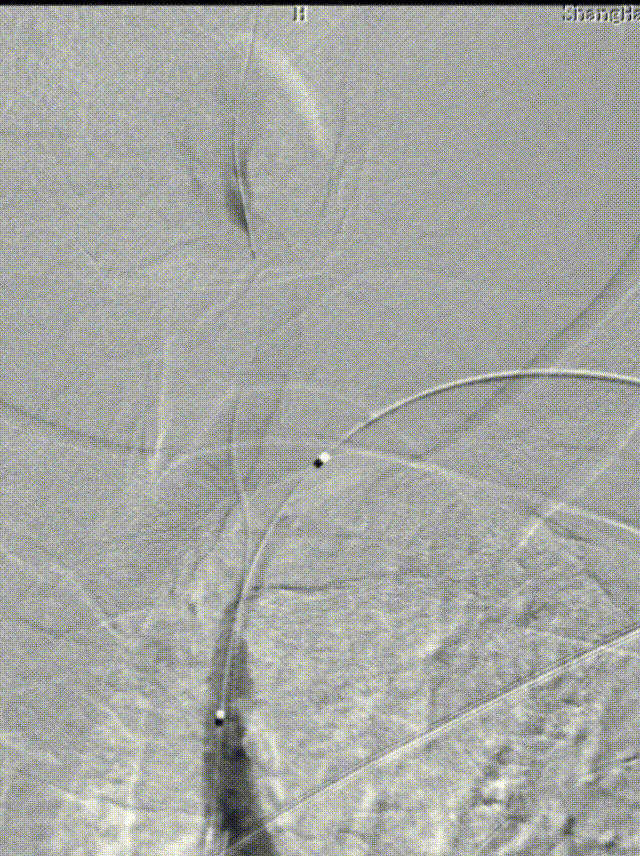

患者出现意识模糊、呕吐、胸闷等不适,查体:血压升高(血压200/100mmHg),神清,对答切题,伸舌居中,查体部分配合,四肢肌力5级,双眼向右凝视伴水平眼震。

立即行Dyna-CT,未见脑出血表现,立即予以尼卡地平及尼莫地平降压,动脉静推负荷量替罗非班。

造影见LV闭塞,立即沿0.014*200cm 通桥北斗SS™神经血管导丝置入3mm*16mm 药物球扩支架至LV1。

压力泵逐渐加压球扩支架到8atm, 支架打开良好,造影示残余狭窄0%。

双侧锁骨下动脉造影见椎动脉、基底动脉血流通畅,远端未见栓塞表现。